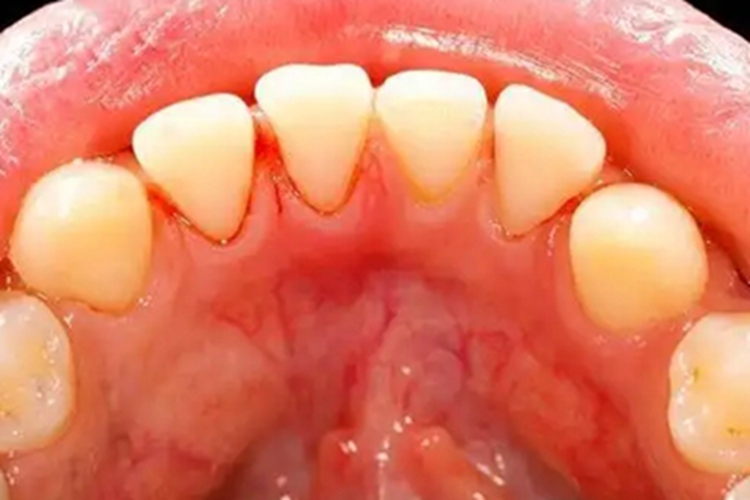

血小板减少性紫癜发病期可见牙龈出血,黏膜上有明显的出血线。本病可能与感染、免疫因素、雌激素水平等有关。

血小板减少性紫癜可引起出血症状,表现为牙龈出血,见局部有鲜红色血液渗出,同时在口腔黏膜上还可伴有明显的出血线。少数患者可有脾大的表现。